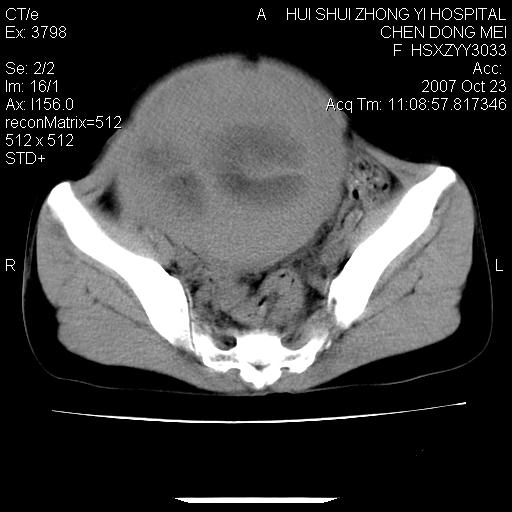

标题: CT10156:女.43岁,发现中下腹部包都块2年 [打印本页]

标题: CT10156:女.43岁,发现中下腹部包都块2年

发现中下腹部包都块2年。2年来月经不规律。

腹腔巨大软组织密度影,边缘光滑,包膜完整,内囊变坏死。腹膜后及盆腔内淋巴结肿大。结合病史考虑卵巢癌可能性大。

病变巨大,呈囊实性改变,包膜较厚且完整,内见分膈,周围脏器明显受压移位,病变与左侧附件关系密切,考虑来源左侧附件的囊腺瘤,不除外癌变可能;畸胎瘤可能性较小。

病变巨大,呈囊实性改变,包膜较厚且完整,内见分膈,周围脏器明显受压移位,病变与左侧附件关系密切,考虑来源左侧附件的囊腺瘤,盆腔内见肿大淋巴结,不除外癌变可能。

病变巨大,呈囊实性改变,包膜较厚且完整,内见分膈,周围脏器明显受压移位,病变与左侧附件关系密切,考虑来源左侧附件的囊腺瘤,不除外癌变可能